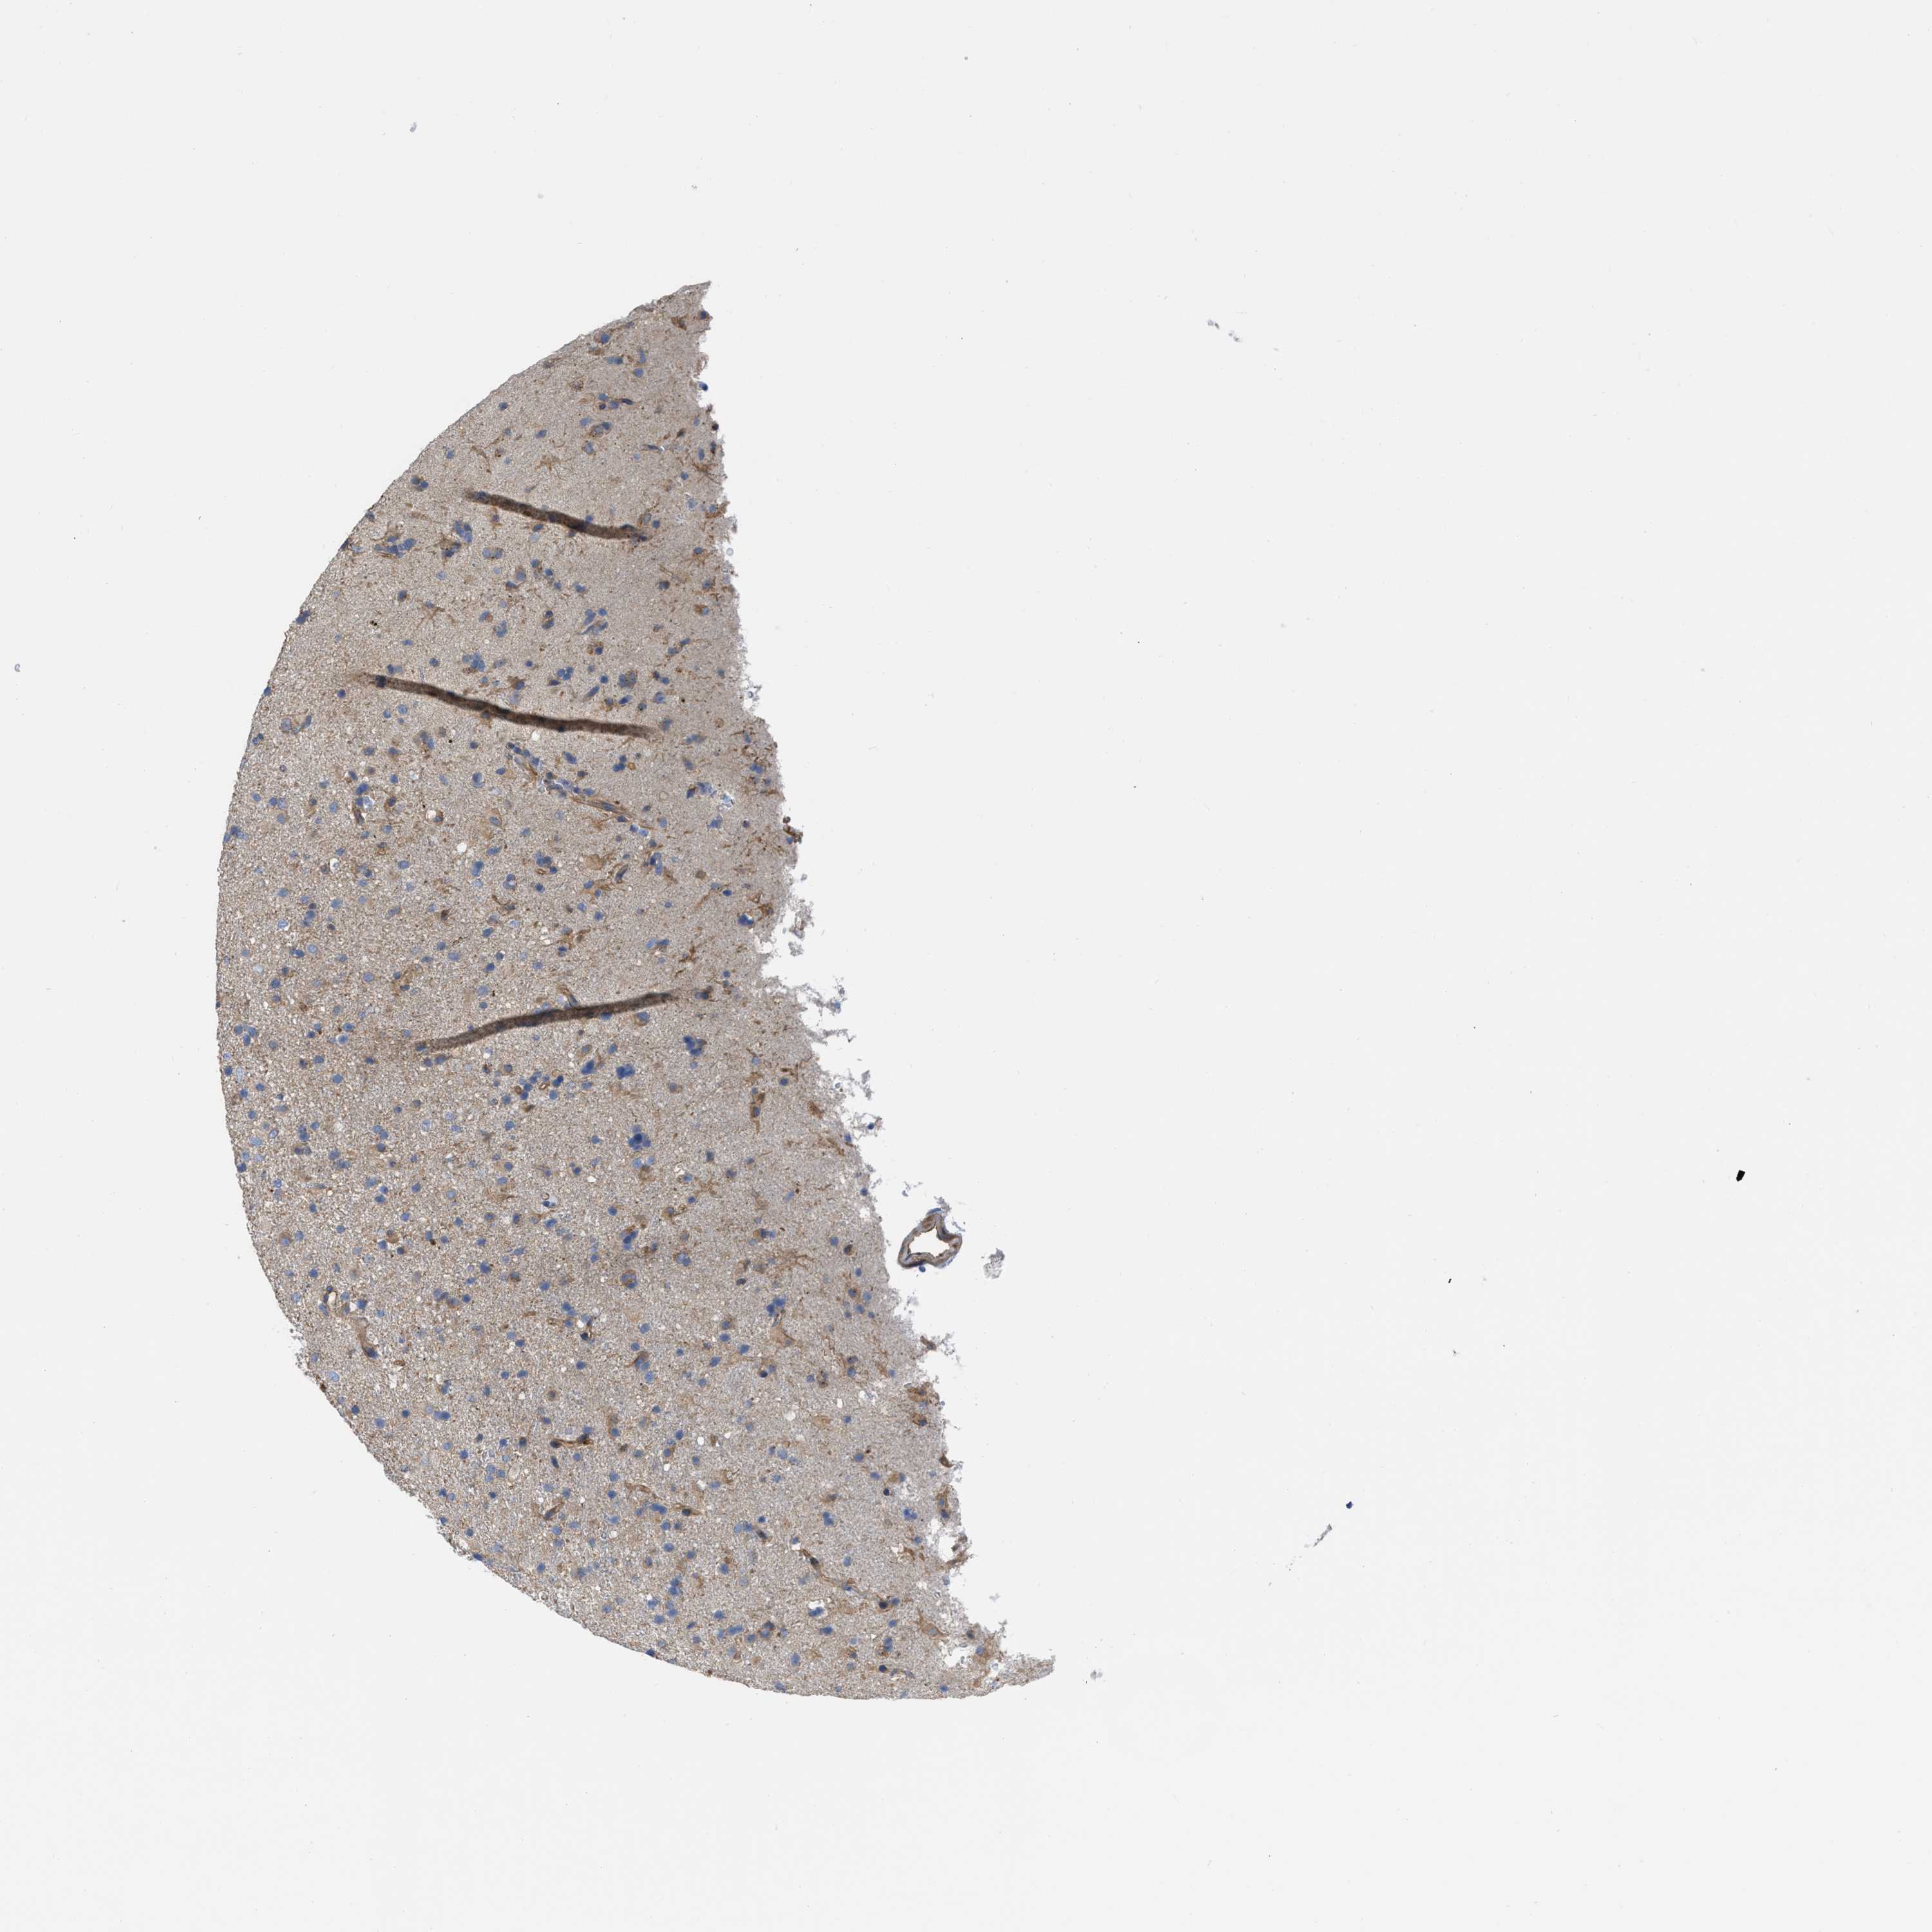

GLIOMA - Protein expressioni

A mouse-over function shows sample information and annotation data. Click on an image to view it in a full screen mode. Samples can be filtered based on level of antibody staining by selecting one or several of the following categories: high, medium, low and not detected. The assay and annotation is described here.

Note that samples used for immunohistochemistry by the Human Protein Atlas do not correspond to samples in the TCGA dataset.

Antibody stainingi

Antibody staining in the annotated cell types in the current human tissue is reported as not detected, low, medium, or high, based on conventional immunohistochemistry profiling in selected tissues. This score is based on the combination of the staining intensity and fraction of stained cells.

Each image is clickable and will lead to virtual microscopy that enables deeper exploration of all samples and also displays staining intensity scores, fraction scores and subcellular localization as well as patient and tissue information for each sample.

Antibody HPA003747

Antibody HPA019769

Glioma, malignant, High grade

Glioma, malignant, NOS

Glioma, malignant, Low grade